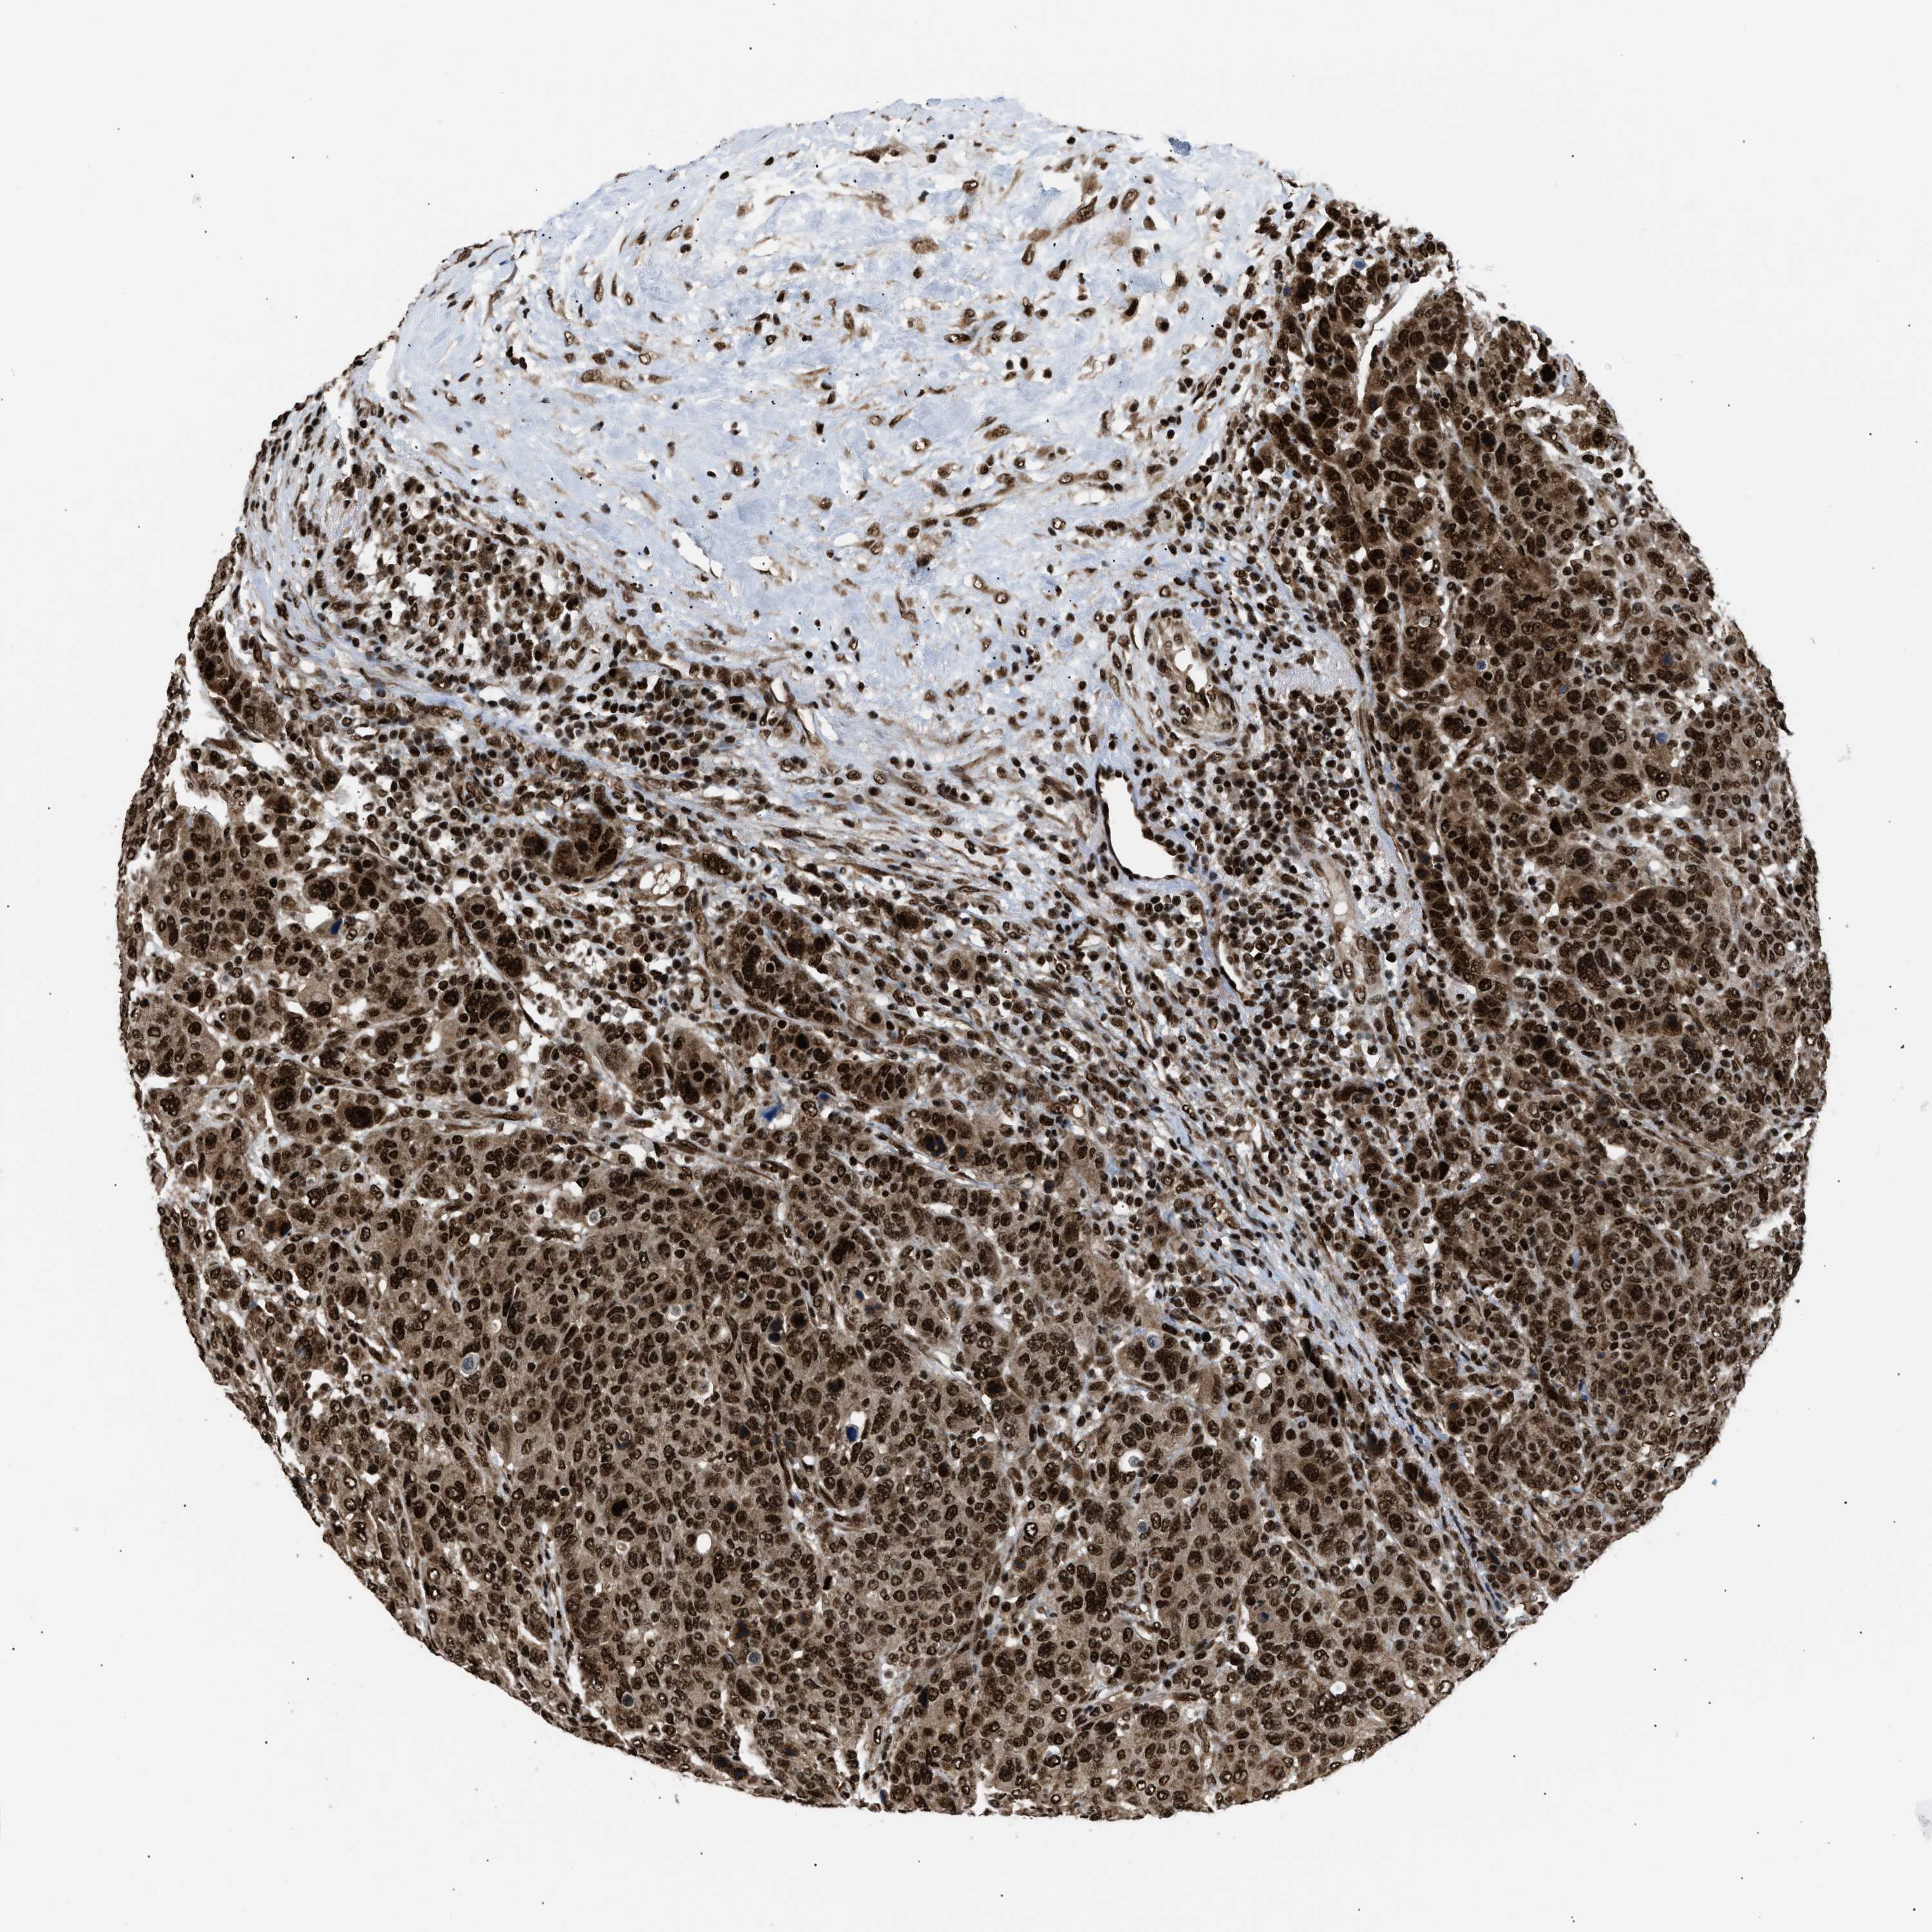

CANCER BREAST CANCER Show tissue menu

BRCA TCGA BRCA VALIDATION PROTEIN EXPRESSION

Breast cancer

Human cancer

Breast invasive carcinoma